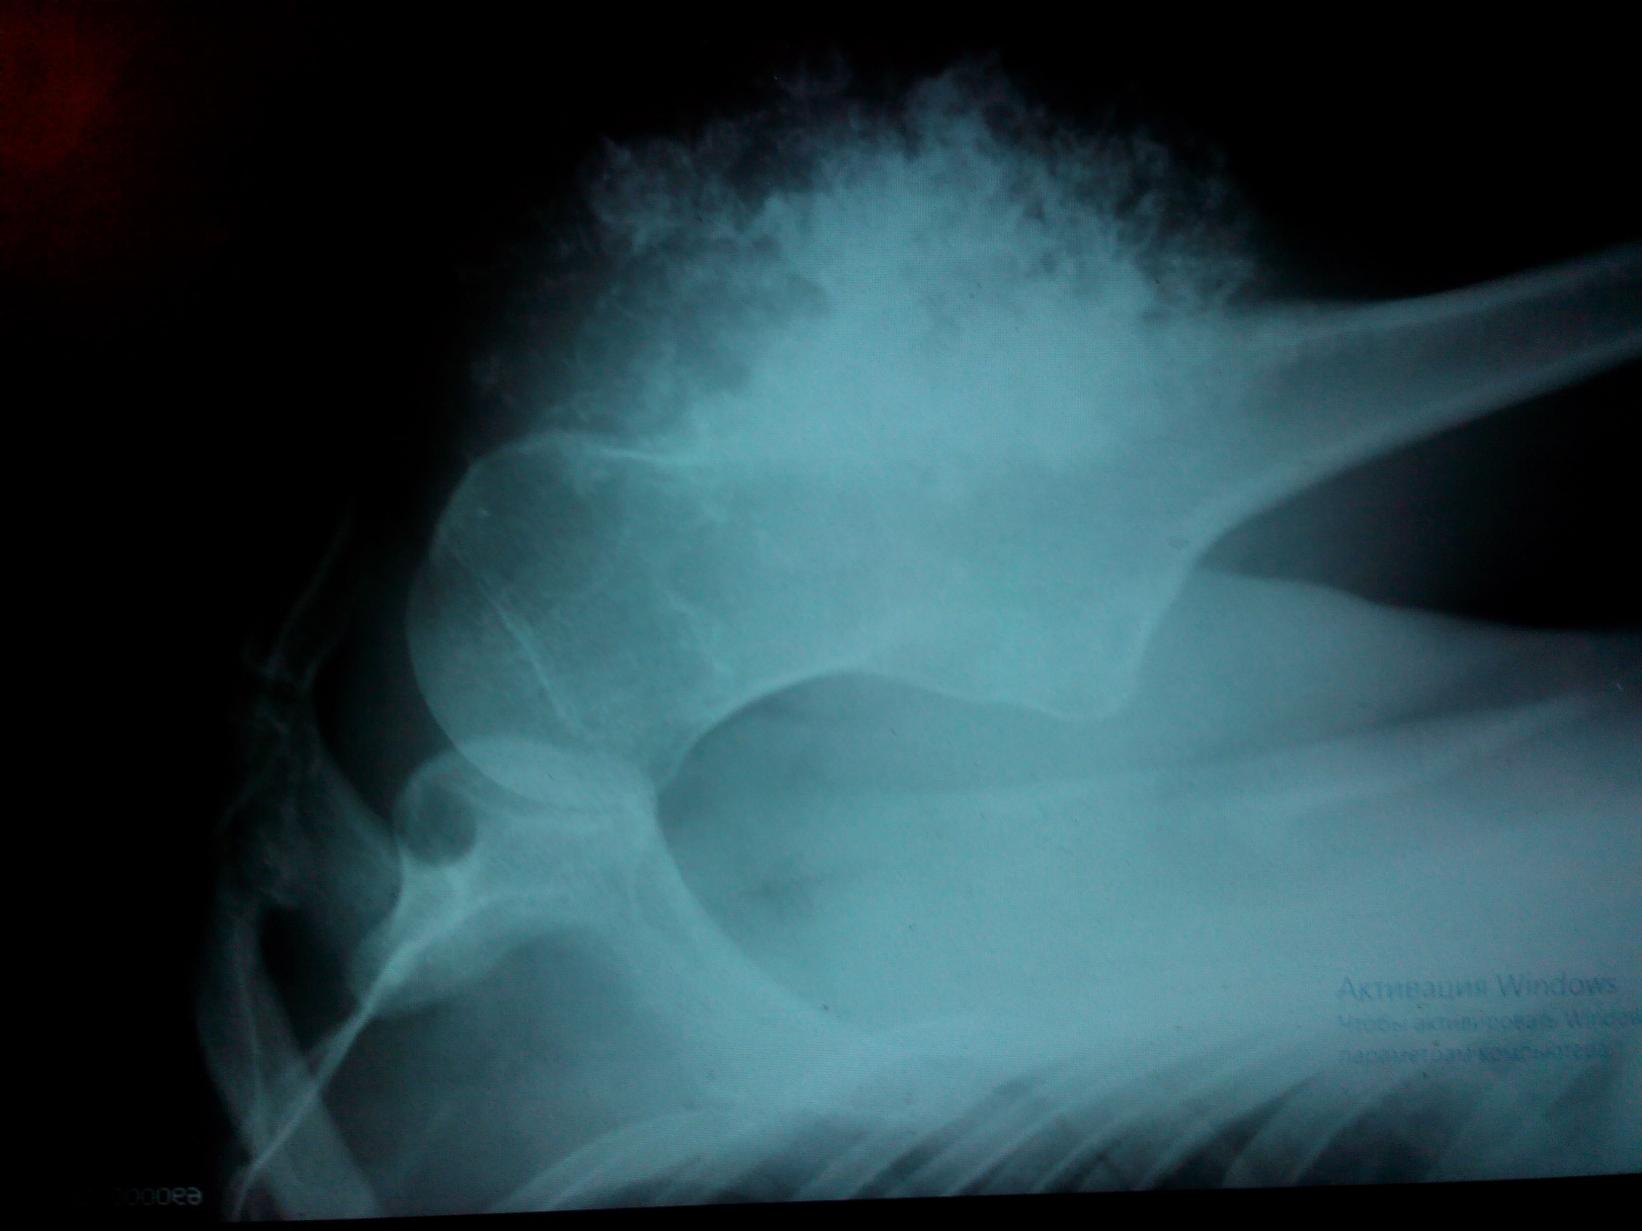

Я 1983 года рождения и после своего тридцатилетия летом 2013 года я заметил на фотографиях что моё левое плечо видоизменилось - стало в окружности больше. По началу я не придал должного внимания и это была моя первая ошибка. Пол года опухоль себя не проявляла в размерах не менялась, но ближе к 2014 года опухоль стала быстро расти. Тут я понял что пора к врачам. Так как наша бюрократия требовала регистрацию я стал оформлять временную регистрацию. Тут я сделал вторую ошибку так как регистрация не требуется потому что медицинский полис привязывается к поликлинике по месту проживания , а не по местурегистрации. Пока оформлял прописку прошло три недели. В начале Февраля 2014 года я обратился в Спб, в Городскую поликлинику №99 и записался на прием к хирургу. Обратился в начале февраля , а номерок на конец февраля. Это была моя третья ошибка - мне надо было попасть на прием к терапевту и это было бы быстрее. На момент когда я пришел к хирургу на прием рост опухоли достиг 10 сантиметров в диаметре. Хирург дал направление на рентген. Рентген кабинет был уже закрыт, снимок сделали только на следующий день. Когда я увидел рентген снимок то я понял что я встрял, только ещё не знал как я встрял. С рентген снимком снова на приём к хирургу и он мне дал направление в СПб ГБУЗ Городская поликлиника № 104

деньги на ветер. Даже далекий человек от медицины поймет что моём случае гистологическое заключение можноподтвердить или опровергнуть без магнитно-резонансной томографии. Мне нужен был диагноз и мне пришлось делать МРТ с подсветкой и обошлось это в 7 000 рублей на 2015 год когда в Спб в частных клиниках цены на аналогичную процедуру были с среднем около 5 000 рублей. После МРТ мне дали заключение и гистолог Алексеева Л.Н. дала патологоанатомическое заключение: хондросаркома G-1. 9220/1. от 03.07.2015

Заключение гистологического исследования: Хондросаркома G2 с разрушением верхней и средней трети левой плечевой кости, 36 см в наибольшем измерении. Врастания опухоли в крупные сосуды невыявленно. Края резекции кости и мягких тканей в не опухоли. 9 подмышечных лимфоузлов без метастазов. pT2bNO(0/9), Stage IB. 28.06.2017 Врач Хейнштейн Валерия Александровна